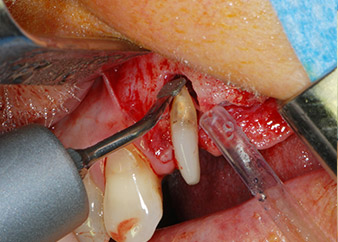

Въпреки това, ние се придържахме към първоначалния си план да запазим и двата зъба като абатмънти за временен мост по време на 6-месечната остеоинтеграция на имплантите. При повторна интервенция, ситуацията трябва да се преразгледа. Първо, в опит да се овладее ендо-перио проблема, останалата повърхност на зъба е внимателно обработена с пиезохирургично оборудване (Piezomed, W&H, използван с накрайник S1 под формата на шпатула, първоначално проектиран за ерозия на латералната синусна стена) (Фиг. 4).

След това апексът се изпилява със същия инструмент, за да се отстрани остатъчната инфектирана апикална тъкан и да се намали възможното допълнително усложнение по кореновите канали (апикоектомия) (Фиг. 5). Ретроградно запълване не е необходимо, защото ортоградното запълване току-що е ревизиран.

периодонциум

Фиг. 4: За да се съхрани зъбът като временен абатмънт, периодонциумът е изпилен с пиезохирургично оборудване...

букален апекс на зъб 24

Фиг 5: ... и букалният апекс на зъб 24 е обработен със същия инструмент (апикоектомия).